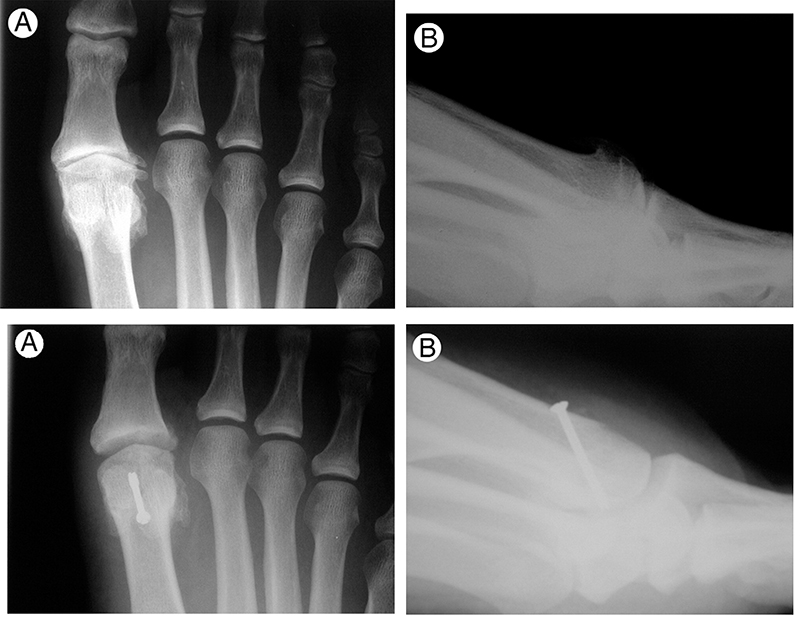

Oa Of The First Metatarsophalangeal Joint (Mpj) Of The Big Toe/Great Toe Is A Common Condition (Hallux Limitus/Rigidus) Marked By Pain, Stiffness, And Impaired Ambulation.

Osteoarthritis of the first metatarsophalangeal joint overview osteoarthritis of the first metatarsophalangeal joint severe joint pain is one of the most common ailments among older adults. Foot pain is a frequent clinical concern. Sometimes patients are told they have a bone spur there, but the real problem is arthritis.

Related To Trauma Or Previous Fracture/Dislocations, Or Abnormal Joint Position As In Hallux Valgus (Bunions)